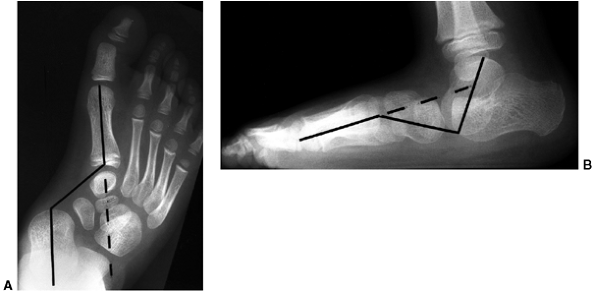

both clinically and radiographically in order to define healthy and

pathologic states. Radiographically, images are always taken in the

standing position, except in the case of infants, for whom position

should be specified. In standing anteroposterior and lateral views of

the foot, the following angles should be determined (Fig. 30.3):

-

The lateral talocalcaneal angle (A)

(lateral view) is measured as the angle subtended by the long axis of

the talus and the plantar surface of the calcaneus. Normally, it is in

the 30 to 45-degree range. It is decreased in the varus foot and

increased in the valgus foot (Fig. 30.3B). -

The anterior talocalcaneal angle (B)

(anteroposterior view) is measured as the angle subtended by the long

axis of the talus and the long axis of the calcaneus. Normally, it is

30 to 45 degrees, decreased in a varus foot and increased in a valgus

hindfoot (Fig. 30.3A). -

Meary angle (lateral view) is the

measurement of the angle subtended by the long axis of the talus and

the long axis of the first metatarsal on a standing lateral view.

Normally, these lines are colinear. In cases where the apex is directed

dorsally, a cavus foot is present. Cases where apex is angled

plantarward are valgus or flatfeet (Fig. 30.3B). -

Intermetatarsal angle (C)

(anteroposterior view) is the measurement of the angle subtended by the

long axis of the first and second metatarsal. This angle is generally

less than 5 degrees but is increased in deformities associated with

bunion formation (Fig. 30.3A). -

The longitudinal arch (D) (Hibb angle,

lateral view) is generally measured as an angle between the plantar

surface of the calcaneus and the first metatarsal. It is decreased in

cavus feet, particularly with a “calcaneus” deformity in which the

longitudinal axis of the calcaneus is increasingly vertical (Fig. 30.3B). -

Calcaneal pitch (E) (lateral view) is

measured as the angle between the horizontal and the plantar surface of

the calcaneus. It is an indicator of the position of the calcaneus in

stance and is particularly important in evaluating a cavus foot or

clubfoot (Fig. 30.3B).

![]() |

Figure 30.3 The standard radiographs of the foot are taken in the standing position, anteroposterior and lateral views. A: On the anteroposterior view (A), the intermetatarsal angle (C) between the first and second metatarsal and the talocalcaneal angle (B) can be measured. B: On the lateral view of the foot, the lateral talocalcaneal angle, the Meary angle, the Hibb angle (D), and the calcaneal pitch (E) should be determined.